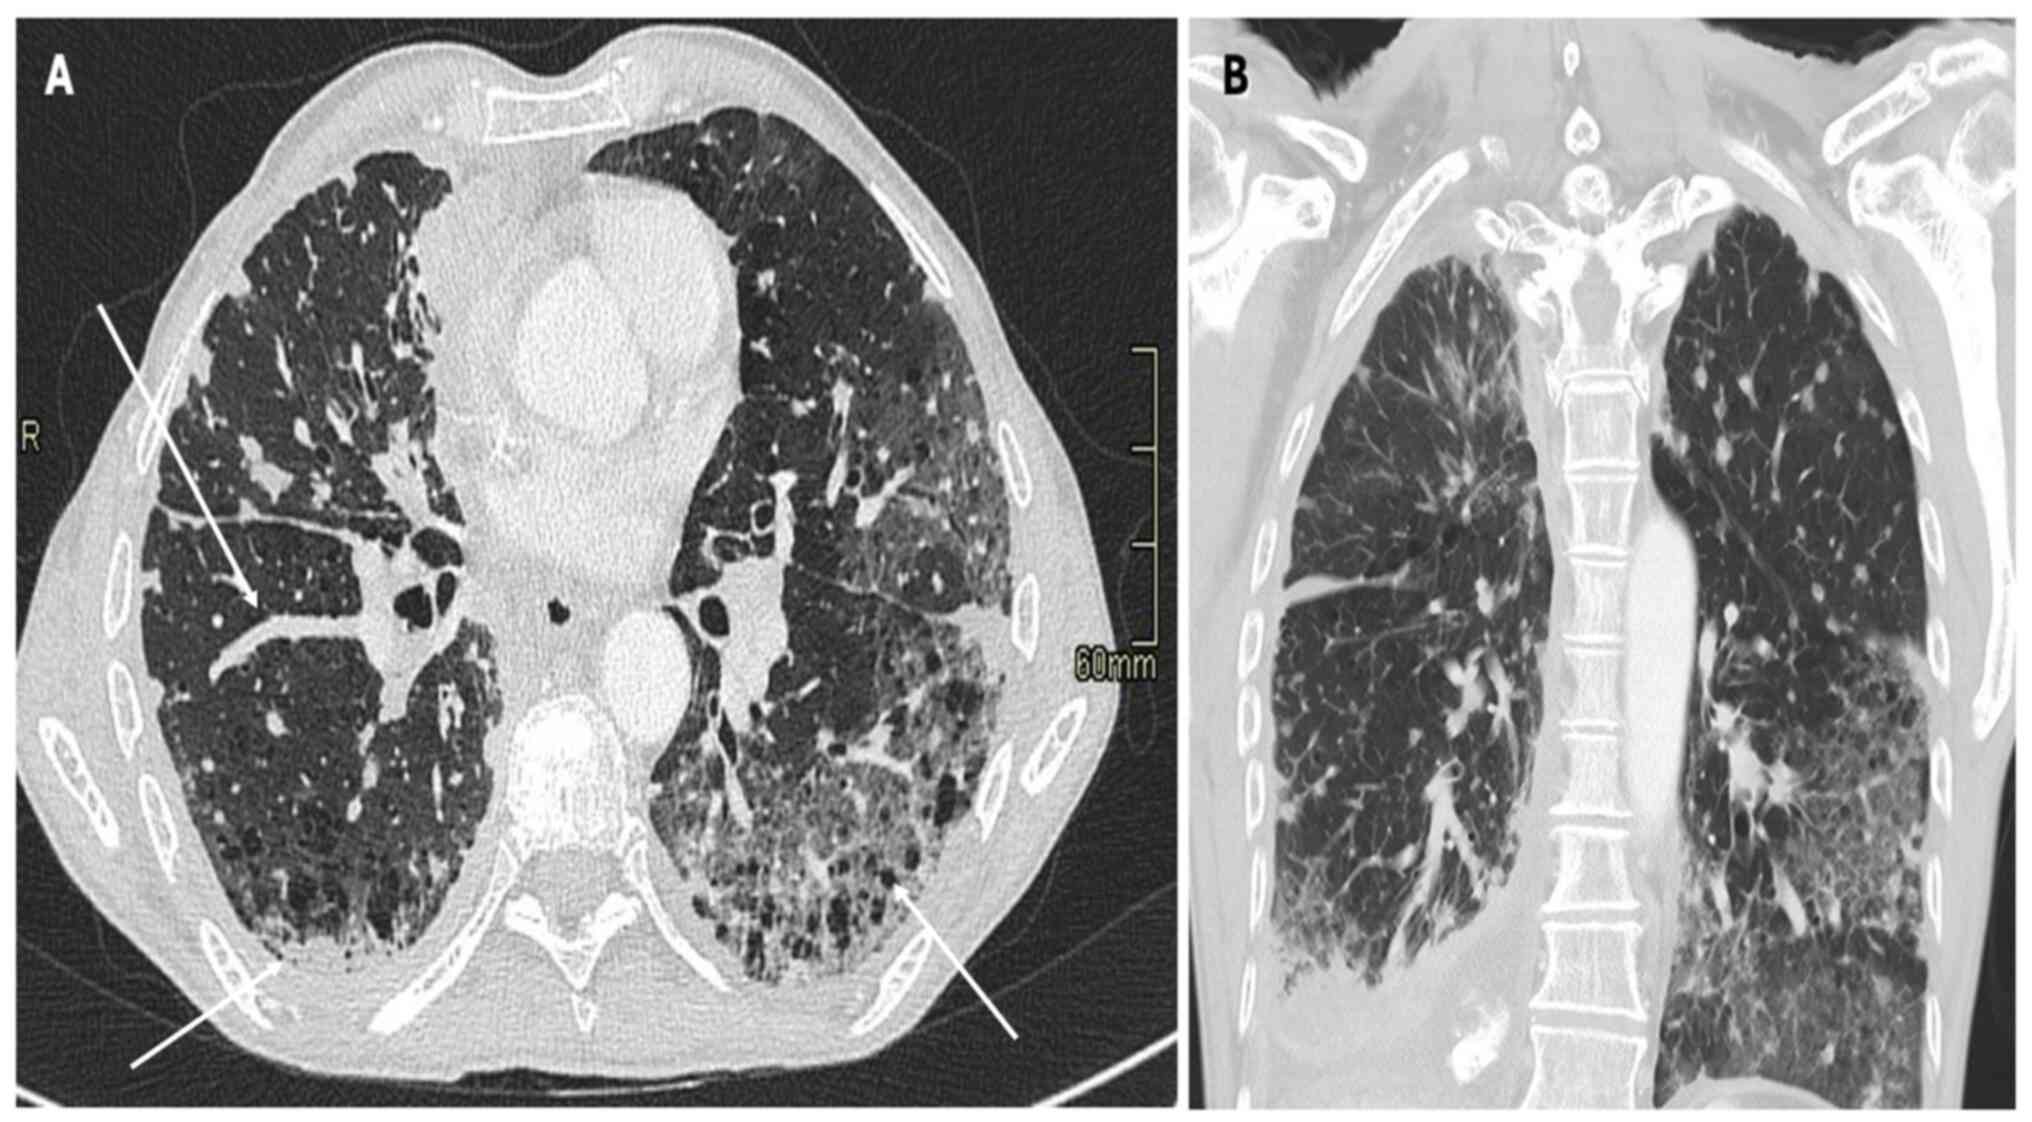

Pneumonitis is a rare irAE following ICI therapy, and it manifests as interstitial lung disease (36). Table II summarizes the main CT patterns observed in ICI-related pneumonitis. Pneumonitis secondary to ICI treatment presents in four distinct patterns: i) Organizing pneumonia (OP); ii) nonspecific interstitial pneumonia (NSIP); iii) hypersensitivity pneumonitis (HP); and iv) diffuse alveolar damage (DAD) (36). While chest X-ray findings in ICI-related pneumonitis may be nonspecific, characteristic abnormalities can aid the diagnostic process (37). Common radiographic manifestations include patchy or diffuse opacities, consolidations and interstitial infiltrates, which may be bilateral and involve multiple lung lobes (37,38). Additionally, air bronchograms or a ‘ground-glass’ appearance may suggest alveolar involvement and inflammatory changes within the lung parenchyma as shown in Fig. 2, Fig. 3 and Fig. 4, which report on a case of gastric, lung and rectal cancer, respectively. However, it is essential to recognize that chest X-ray findings alone may not be sufficient to diagnose or exclude pneumonitis (37) definitively. Further imaging with CT of the chest is often necessary to delineate the extent and nature of pulmonary abnormalities and guide subsequent management decisions (38).

Figure 4

(A) Axial and (B) coronal CT scan with lung parenchyma reconstruction depicting a 58-year-old female patient with metastatic rectal adenocarcinoma with progressing pulmonary metastases undergoing experimental immunotherapy with Nivolumab (see white arrows). Note several areas of increased parenchymal density, predominantly perilesional, characterized by ground-glass opacity (see orange arrows).